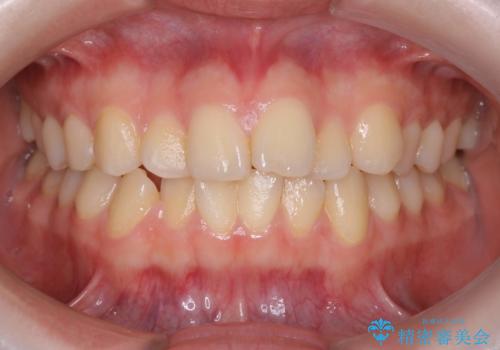

インビザラインによるガタつきの矯正治療 シンプル・短期間

- 20代女性

- invisalign full

- 1年6ヶ月

- 非抜歯、IPR+拡大によるマウスピース矯正を計画した。

一見前歯のガタつきだけのように見えても、そのガタつきの根本的な原因が奥歯の位置であったりすると、マウスピースの枚数がそれなりに多くなり、治療に時間がかかることもあります。